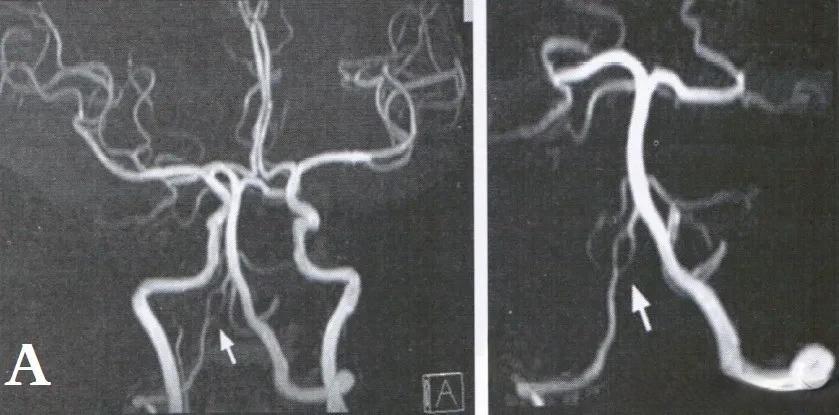

对于椎动脉开窗畸形的确诊,颅脑磁共振血管造影术(MRA)和CT血管造影(CTA)是目前最常用的影像学检查方法。MRA具有无创、无辐射、无需对比剂等优点,能够清晰显示椎动脉开窗畸形及其合并的其他血管异常。CTA则能够提供更详细的血管解剖结构信息,对于评估病变范围和制定治疗方案具有重要价值。

一位69岁的女性患者就出现了这种情况。她有高血压和糖尿病病史,入院时主诉心前区隐痛,并伴有头晕症状。经检查发现,她的左侧椎动脉内径仅为2.0毫米,彩色多普勒超声显示管腔内有双向血流,频谱多普勒于收缩早期探及反向血流频谱,速度达到69厘米/秒。这种异常的血流动力学改变,正是椎动脉开窗畸形的典型表现。